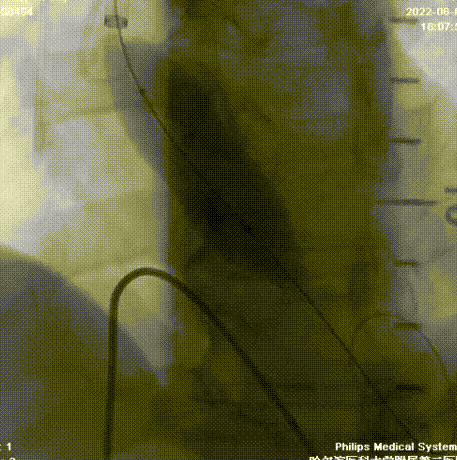

术后缝合和按压

最终结果

术后24h超声显示:瓣口流速: 2.4m/s;LVEF值:39%;人工瓣膜紧密贴合根部,功能正常 、心衰情况显著改善。